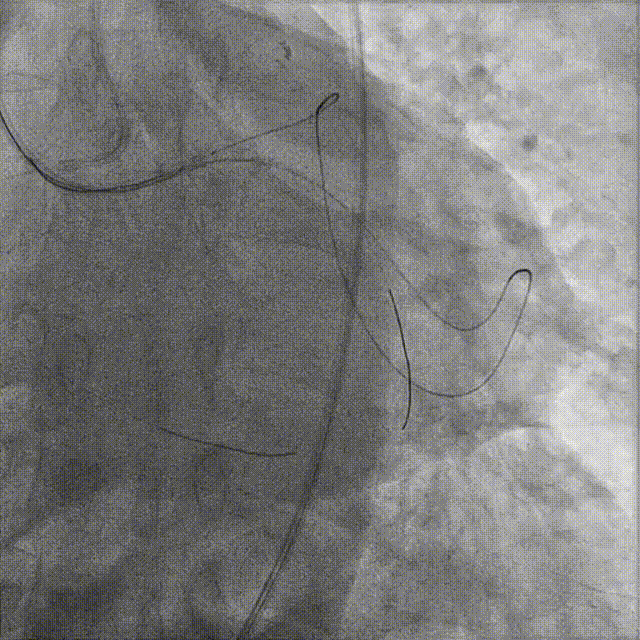

置7F UBS 3.75、6F JR 4.0指引导管至左右冠开口,分别送入Marvel导丝至LCX远段、RCA远端加强支撑,行双侧造影。

在微导管支撑下,Sion导丝无法经OM1心外膜侧枝逆向至LAD远段,改送Fielder XT-R导丝逆向至LAD远段。

HighTrack微导管跟进至闭塞病变远端,正向工作导丝做指引,应用Fielder XT-A导丝逆向通过闭塞段至LM内,反复尝试调整导丝未能进入正向指引导管。